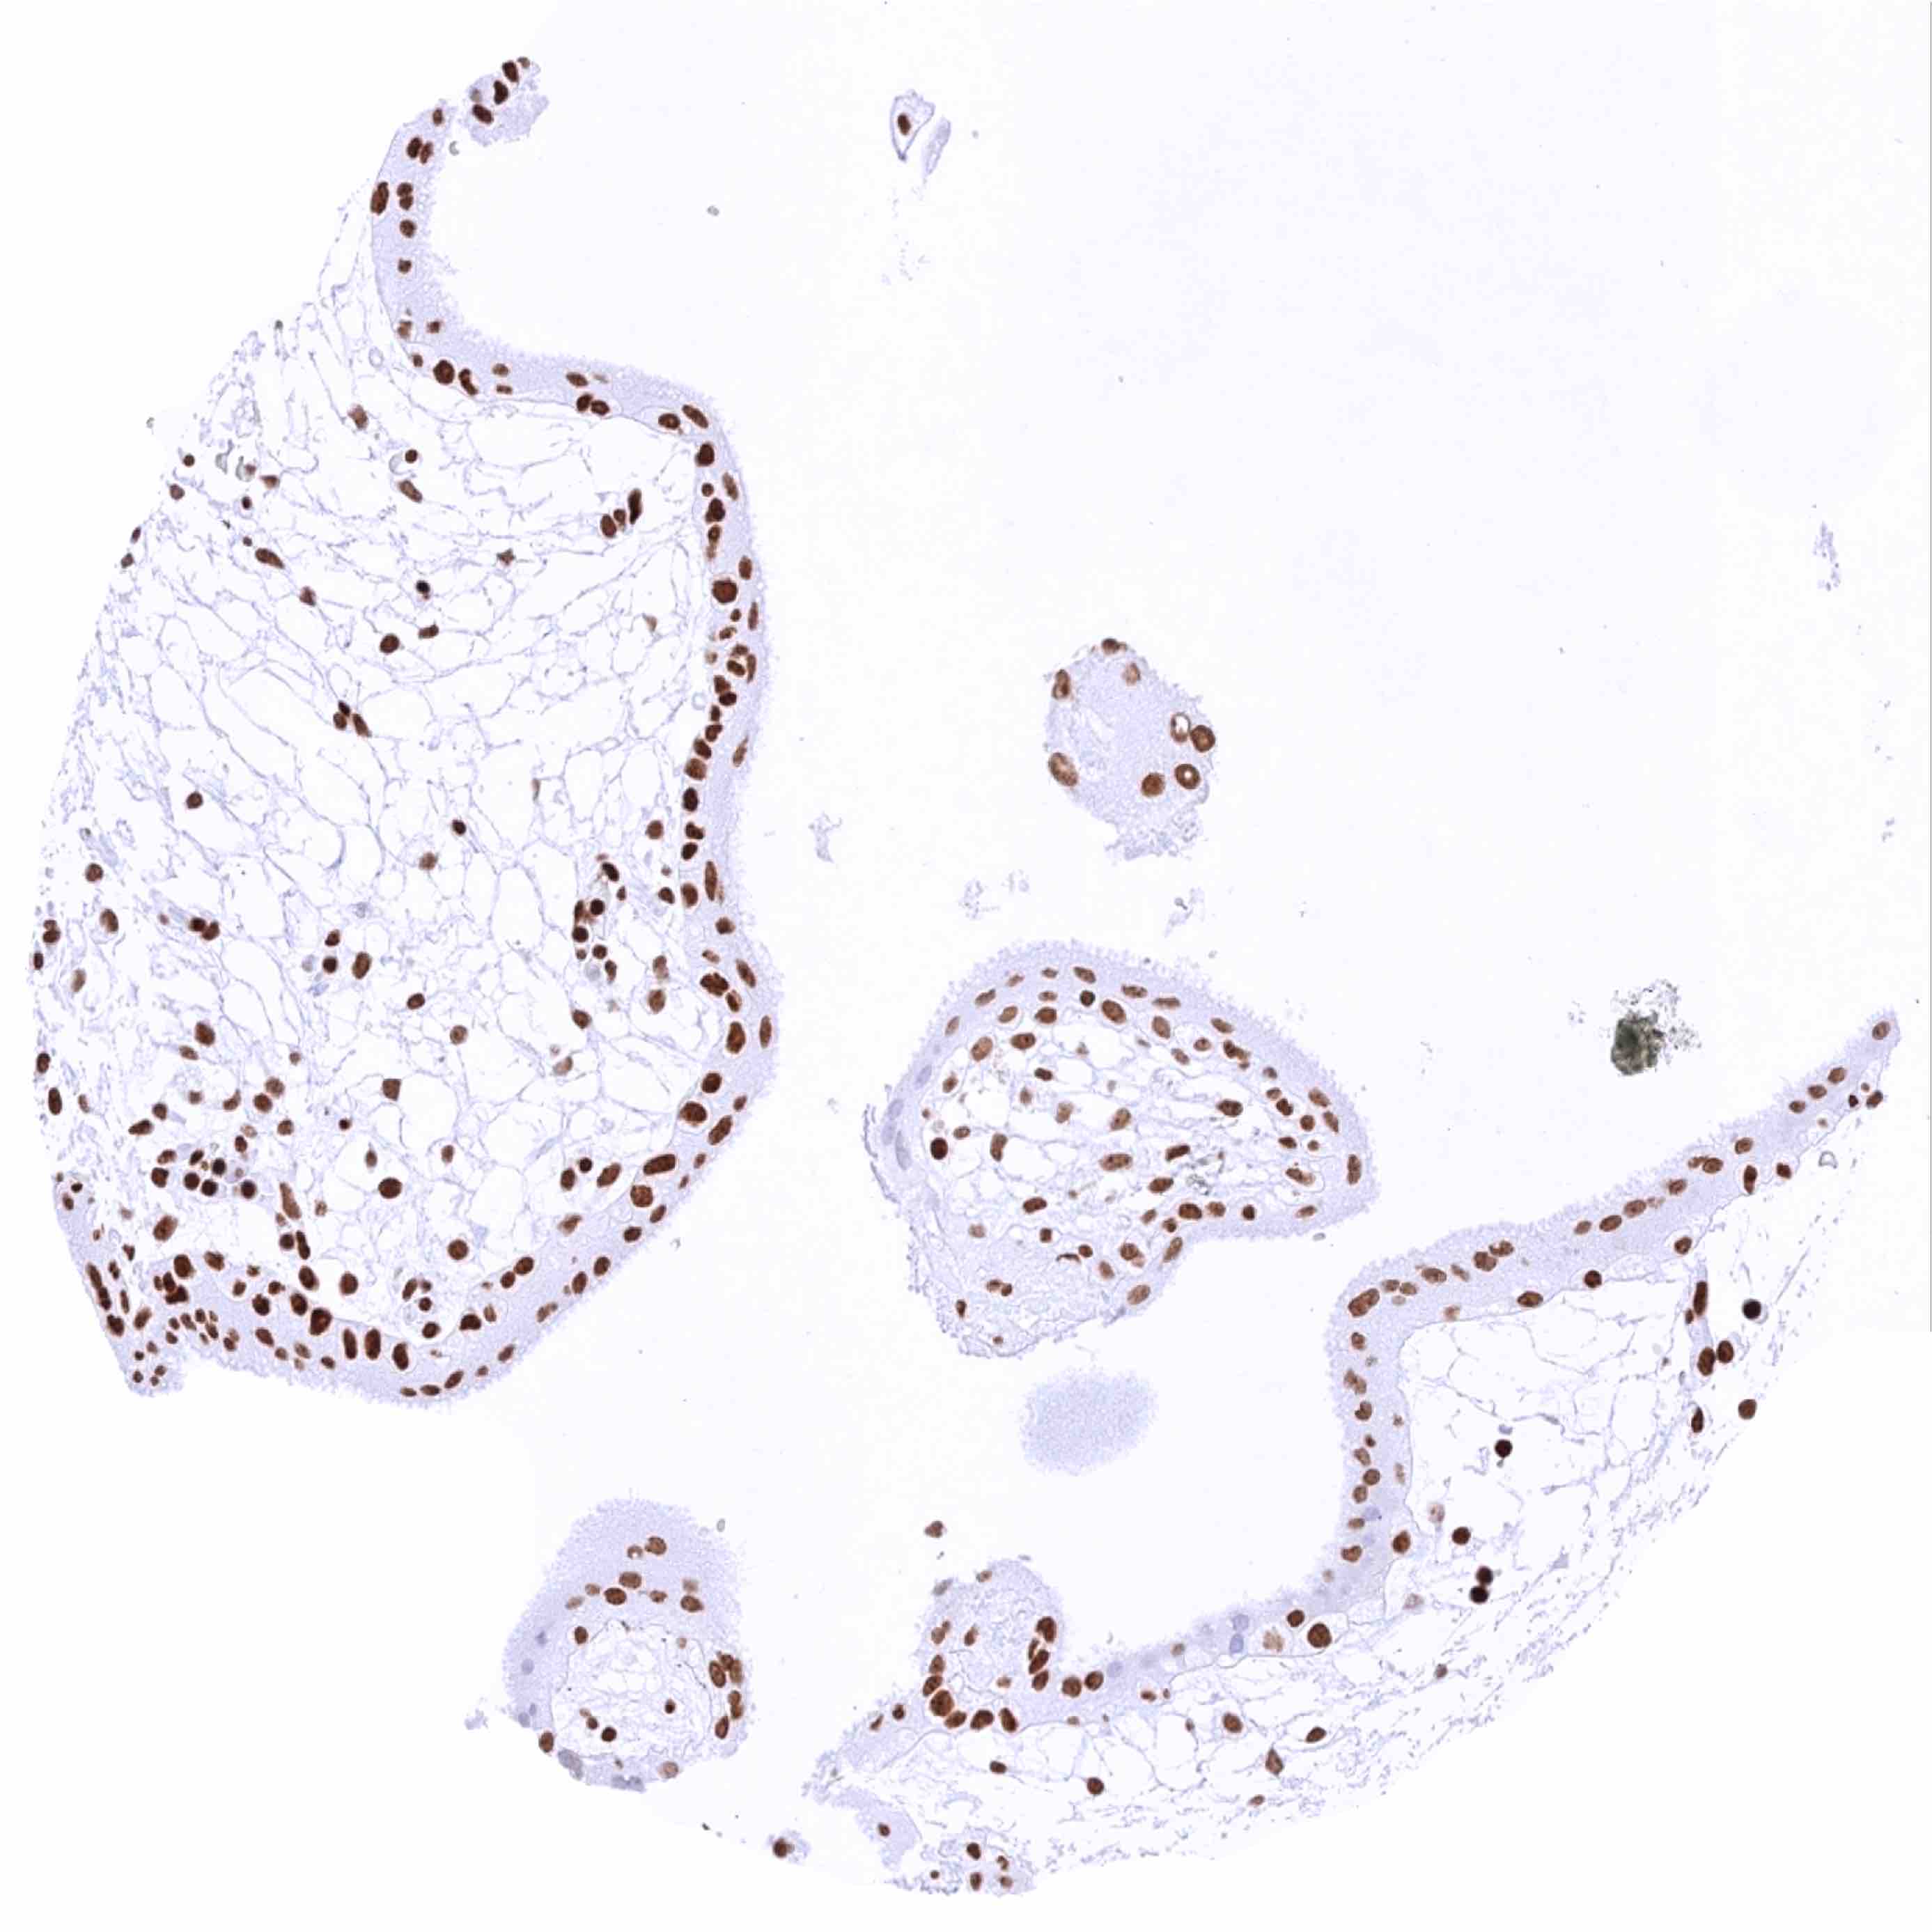

Placenta (amnion and chorion) – Strong nuclear HMGB1 staining of chorion cells, moderate nuclear HMGB1 staining of amnion cells